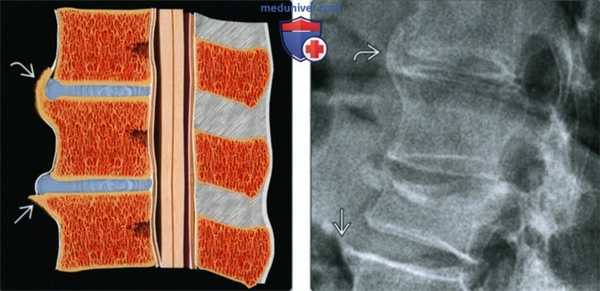

(Слева) Рисунок: первичные горизонтальные остеофиты, которые формируются в результате вытягивания шарпеевских волокон на фоне выпячивания фиброзного кольца. Таким образом, деформирующий спондилез или формирование остеофитов тел позвонков связан с дегенеративным процессом в межпозвонковом диске. По мере роста остеофиты приобретают вертикальную направленность и могут перекрывать пространство диска.

(Справа) Рентгенография в боковой проекции: горизонтальный остеофит из кортекса тела позвонка и более крупный перекрывающий остефит.